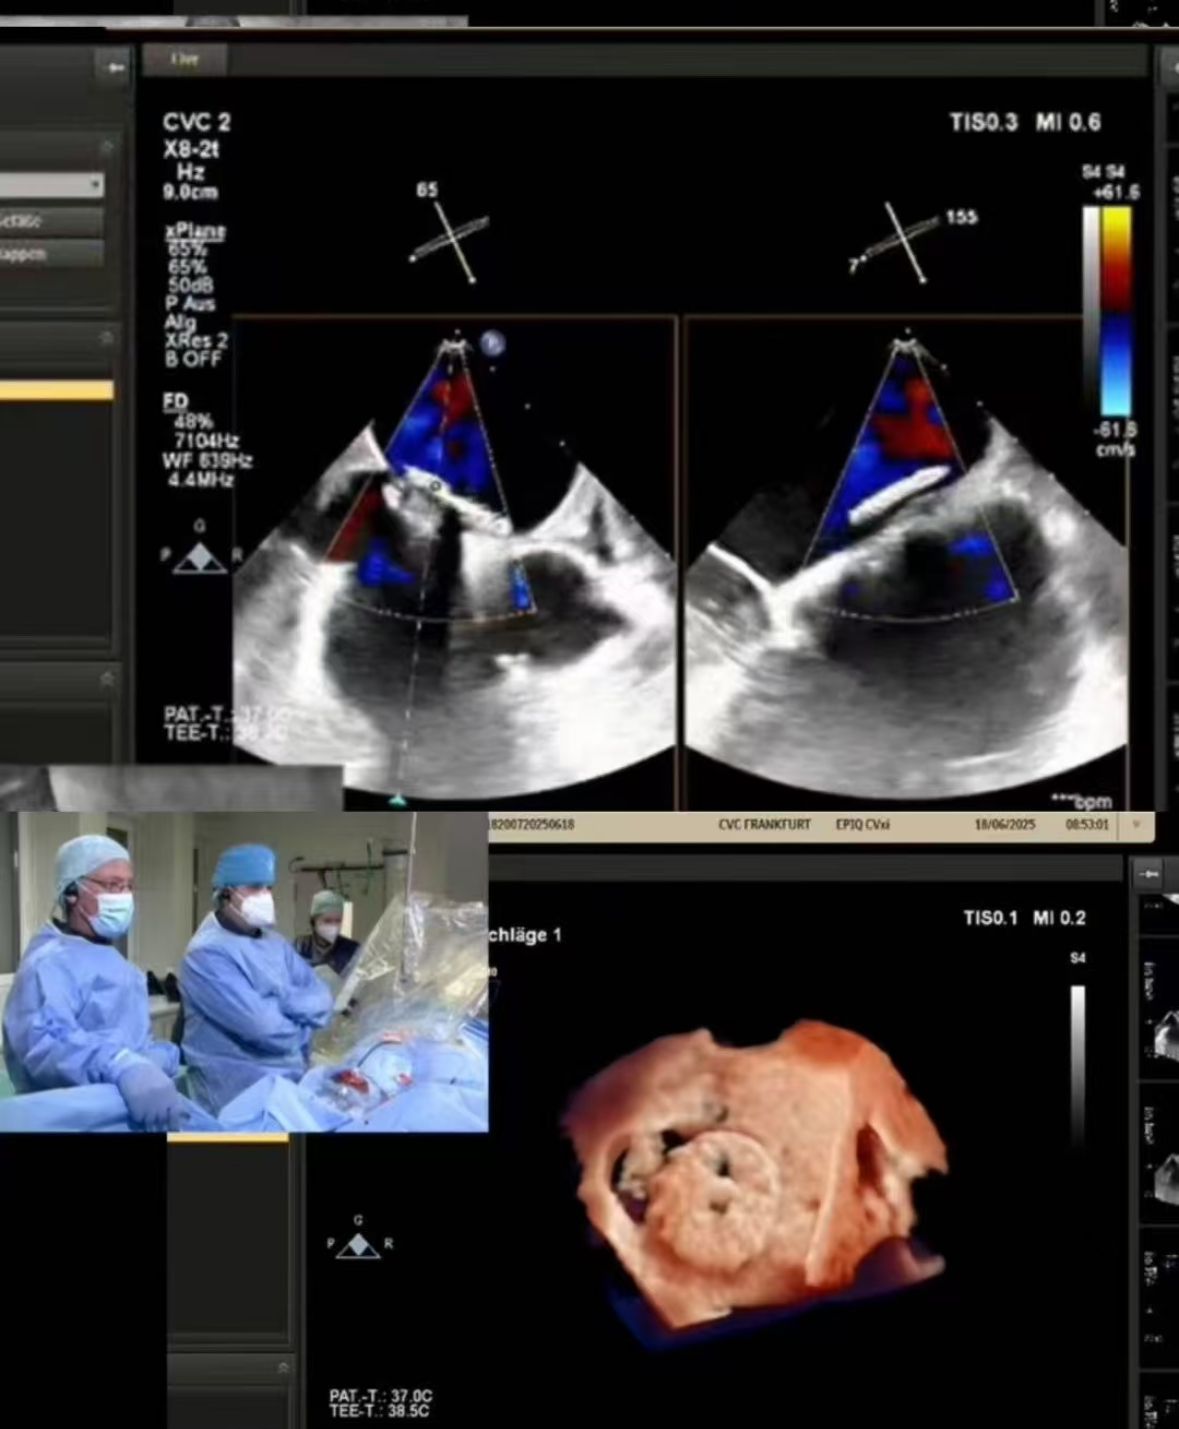

Thrilled to showcase our MemoSorb PFO Occluder – the world's first absorbable device (degrades to water & CO₂ within 1 year) – during a live broadcast from the Blue Room at CSI Frankfurt!

Nós transmitimos um fechamento complexo do FOP realizado no CVC Frankfurt em uma paciente do sexo feminino de 60 anos com:

1. AVC embólico recorrente (2014, 2021)

2. Alergia severa do níquel (contra-indicação para dispositivos do metal)

3. Shunt residual após o fechamento prévio

2. Fechamento preciso: Imagem em tempo real guiou a implantação perfeita na anatomia desafiadora (fenestração do túnel PFO).